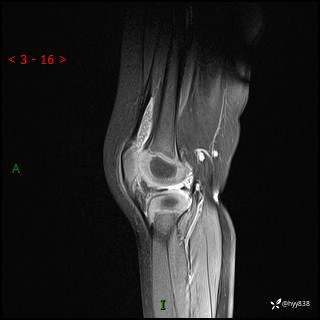

现病史:患儿1月前无明显诱因出现左下肢跛行,伴左膝关节红肿,无发热、咳嗽、恶心、呕吐等症,于当地医院就诊行X线片未提示异常,今至我院门诊就诊,门诊医师拟“跛行待查”收入院。 病后,患儿精神、食欲可,睡眠欠安,大小便通畅,体力体重无明显下降。

左膝MRI平扫